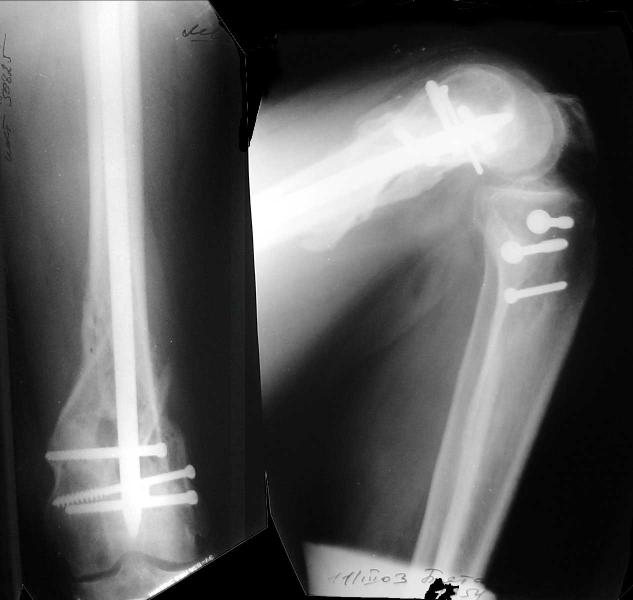

This is what we have done... As generally true for LISS look at the bone not the hardware.

There are two more srews above. The one not completely in got damaged head.

And why LISS is superior here than nail?

Look what we would have done.